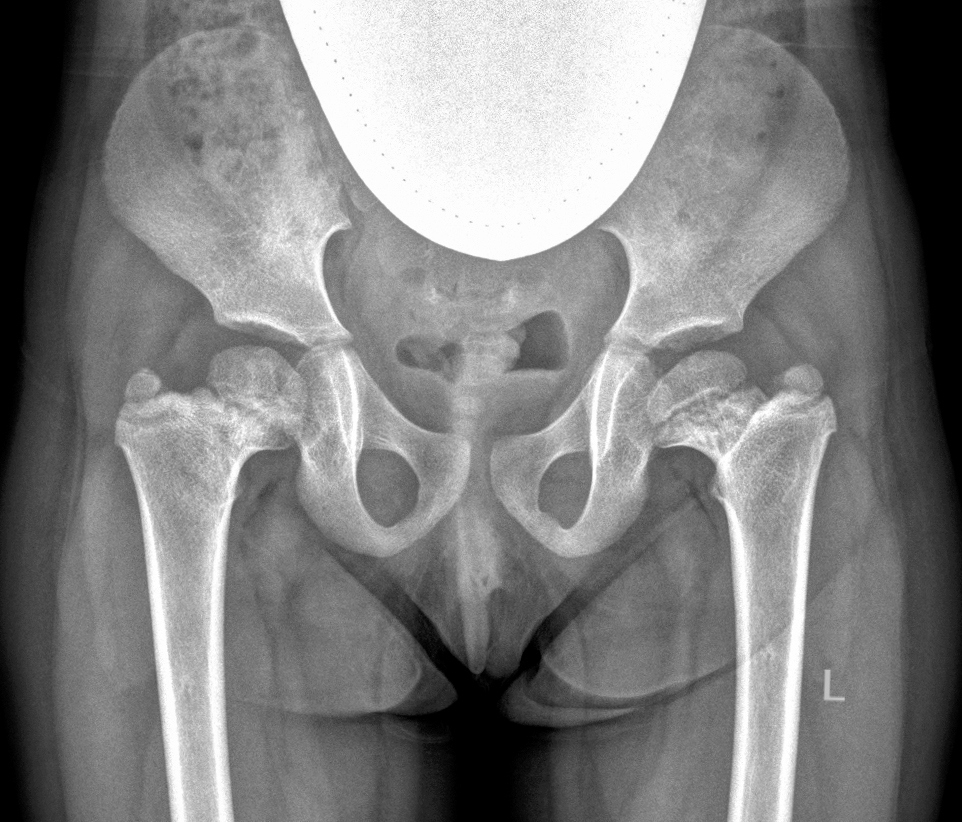

5) другие причины — 5 (1,3 %) детей. В эту группу вошли пациенты с неуточненной или редкой причиной поражения тазобедренных суставов, например, вследствие применения метода экстракорпоральной мембранной оксигенации в периоде новорожденности [13] (рис. 5).

Рис. 5. Рентгенограммы пациентки Г., 4 года. Формирующееся высокое положение большого вертела с двух сторон, дистрофические изменения шейки бедренной кости. Случайная находка на рентгенограмме, выполненной в 3 года в связи с проявлениями транзиторного синовита тазобедренных суставов после перенесенной острой респираторной вирусной инфекции: а — прямая проекция; б — проекция по Лауэнштейну